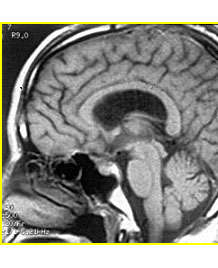

沈建康主任論文:顱內(nèi)巨大動(dòng)脈瘤的顯微外科手術(shù)治療

沈建康主任論文:鞍結(jié)節(jié)腦膜瘤的手術(shù)入路和技巧

作者: 沈建康 趙衛(wèi)國(guó) 卞留貫 濮春華 蔡瑜 發(fā)表于: 中華神經(jīng)外科雜志 摘要 目的: 探討鞍結(jié)節(jié)腦膜瘤的手術(shù)入路和手術(shù)技巧,以改善手術(shù)治療的效果。 方法:回顧性分析我科1985年1月至2004年12月手術(shù)治療的...【詳細(xì)】

(專家解讀)癲癇發(fā)病的因素有哪些?

癲癇疾病給患者的身心健康帶來(lái)了嚴(yán)重的危害,生活中有很多的因素會(huì)引起癲癇發(fā)作,但因?yàn)楹芏嗳瞬涣私膺@種疾病,所以很多患者會(huì)很糾結(jié)。平時(shí)我們的生活很規(guī)律,也沒(méi)有抽煙喝酒的壞習(xí)慣,也沒(méi)有其他的壞毛病...【詳細(xì)】

侯增欣教授訪談:如何識(shí)別腦腫瘤早期信號(hào)?

大多數(shù)人都有這樣一種概念:得了腦瘤似乎就等于被判了死刑。確實(shí),因?yàn)槟X功能的舉足輕重,腦瘤比起其它部位的腫瘤,對(duì)生命的威脅更大也更嚴(yán)重,但是,隨著現(xiàn)在醫(yī)療技術(shù)的發(fā)展,讓我們對(duì)腦瘤有了更全面的了...【詳細(xì)】

侯增欣教授訪談:腦瘤究竟有多可怕?

如今,高科技產(chǎn)品如手機(jī)、電腦等成了我們隨身不離的伙伴,然而享受著高科技帶來(lái)的便利同時(shí),人們也越來(lái)越擔(dān)心其輻射會(huì)引發(fā)腦腫瘤。而一旦患上了腦腫瘤,似乎離死亡就不遠(yuǎn)了,就算搶救過(guò)來(lái),也是廢人一個(gè)。...【詳細(xì)】